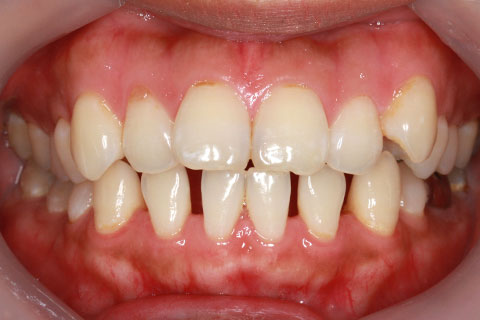

ハーフリンガル矯正1:上の歯のみ舌側矯正で治療(矯正期間20ヶ月)

- 年齢・性別

- 22歳女性

- 治療期間

- 1年8ヶ月

- 抜歯

- 上顎4番抜歯

- 治療費

- 110万円(税込み)

- 備考

- ハーフリンガル矯正

- 治療内容

- 上下前歯部凸凹の改善

- 施術の副作用(リスク)

- 裏側矯正では装置に慣れるまで発音しづらい場合がある。矯正治療に伴うリスクと治療限界についてはこちらをお読みください。